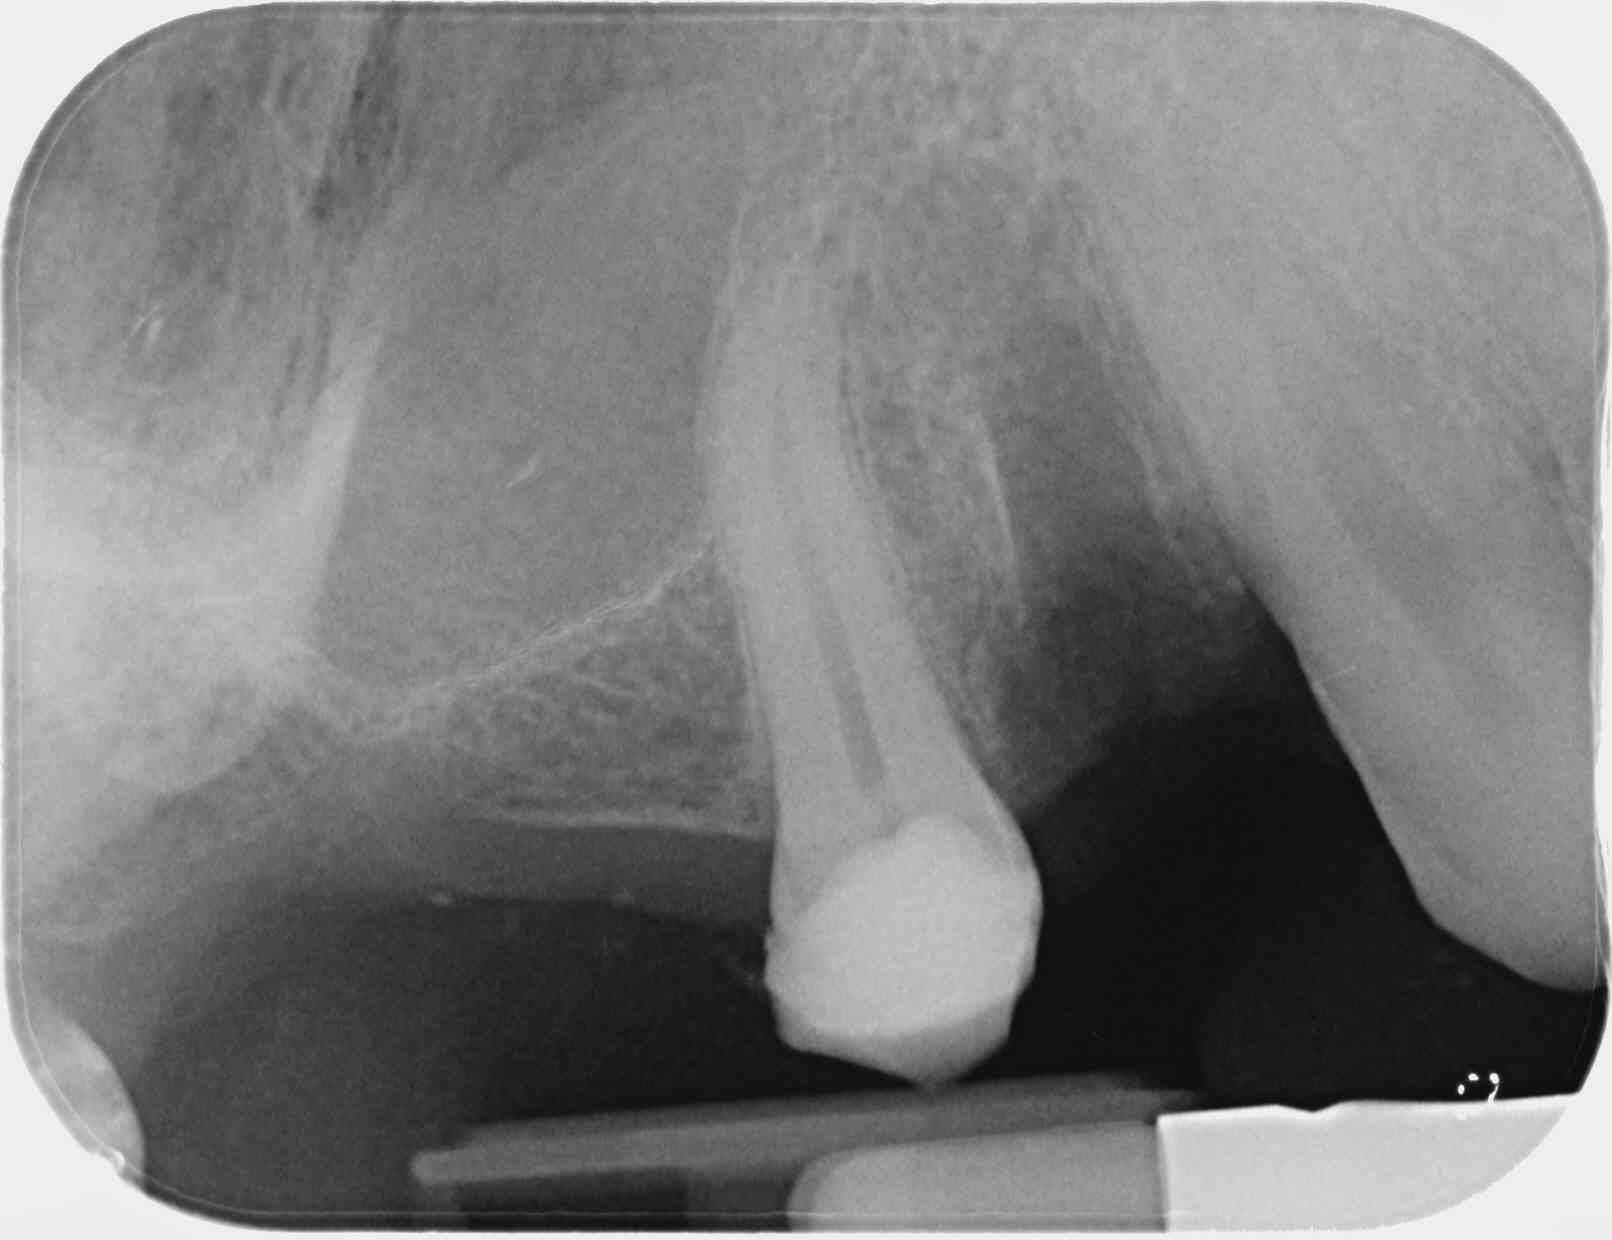

J'aurai mis ma main à couper, en regardant la pano, que la 15 était dépulpée.

Et non.

Entre la pano et la rétroalvéolaire, j'ai seulement réalisé les extraction et posé un CVI sur la 15.

On ne voit aucune ligne de manière nette, les dents ne sont pas bien individualisées, et paraissent comme ankylosées (on ne voit pas le desmodonte...). C'est pas nette du tout!

Une bonne pano doit te permettre de voir les différentes structures dentaires (émail, dentine, etc) et péridentaires (le desmondonte notamment), les caries, etc...

Cela ne m’étonne pas que tu puisses voir une obturation là où il n'y en a pas... Rien n'est bien délimité dans ta pano.